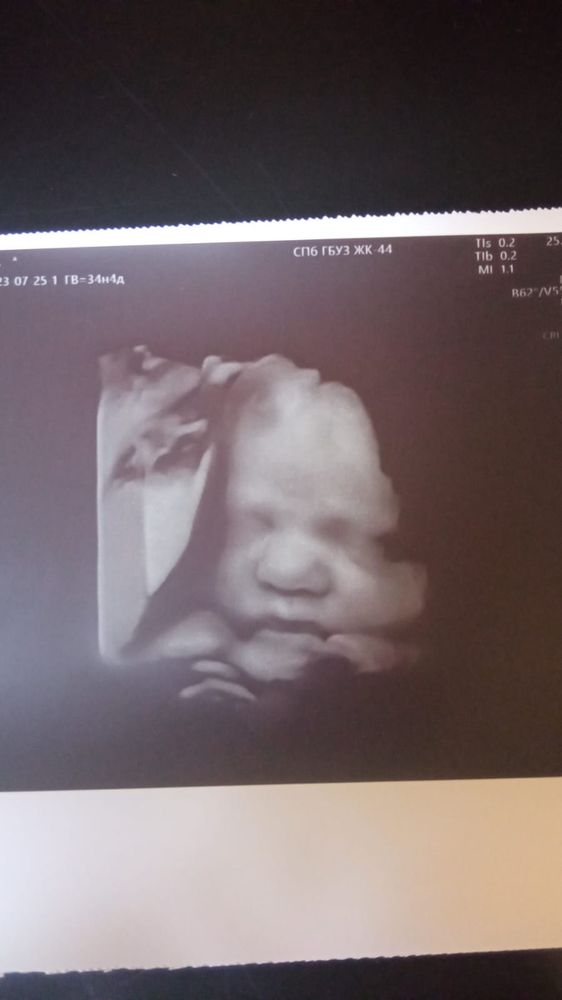

3 скрининг Ил УЗИ в, 34 недели и 4 дня

Малышка в порядке, по параметрам на 34-35 недель. Весит 2165 гр, ростом 46 см. Длинноногая крошка) Всё у нас хорошо, плацента, по ходу, приподнялась, не стареет ещё, вод достаточно. Срок ставят на 8 сентября. Что ж, не плохо) . Единственное, в правой маточной артерии повышен какой то ПИ. Но, как сказала врач, всё компенсируется и никаких телодвижений не надо. Только контроль КТГ. Что это за зверь(в смысле ПИ) я не гуглю. В пятницу к врачу, всё узнаем. И, фото моего щекастика. Кстати, ходила мамой. Она вообще впервые видела малыша на УЗИ. Плакала даже)))